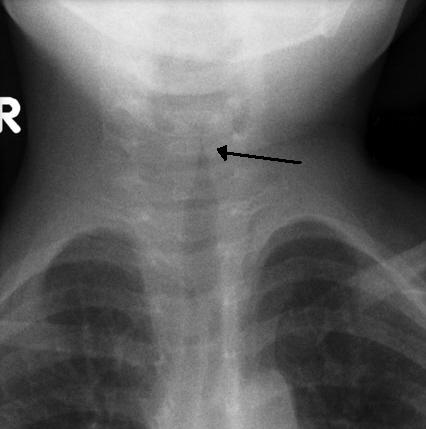

Когда возникает подобная ситуация, специалисты проводят рентгеновское исследование горла, которое позволяет определить масштабы отека. Рентгенограмма в боковой проекции демонстрирует увеличение размеров надгортанника.

Для определения возбудителя эпиглоттита у детей проводится лабораторная идентификация, которая включает в себя бактериологическое исследование мазка из зева и посев крови на аэробные и анаэробные бактерии. Также проводится рентгенография шейного отдела позвоночника в прямой и боковой проекциях для выявления увеличенной тени надгортанника (так называемый «симптом большого пальца»).